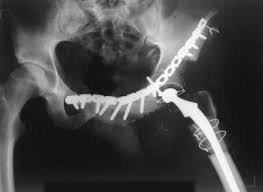

Surgical removal of the cancer may be considered for pelvic cancer patients.

Bone cancer can begin in any bone in the body, but it most commonly affects the pelvis or the long bones in the arms and legs. There are many pelvic cancer symptoms a person can experience. Bone cancer develops in the skeletal system and destroys tissue. The symptoms of bone cancer are: In contrast, some other metastatic tumors, such as those from the prostate, are commonly osteoblastic, meaning that they form new bone and increase the brittleness of the bones. Rarely, people with a bone sarcoma may have symptoms such as fever, generally feeling unwell, weight loss, and anemia, which is a low level of red blood cells. Although breast cancer can spread to any bone, the most common sites are the ribs, spine, pelvis, and long bones in the arms and legs. Osteosarcoma is probably the most common disease that is related to pelvic bone cancer, with chondrosarcoma following close behind it. A primary bone cancer is one that starts from bone. Although less often, other areas (such as the ribs) may be affected. Can bone cancer be found early? Hip pain is a common complaint like that of knee or back pain. Get the latest health information from mayo clinic delivered to your inbox.